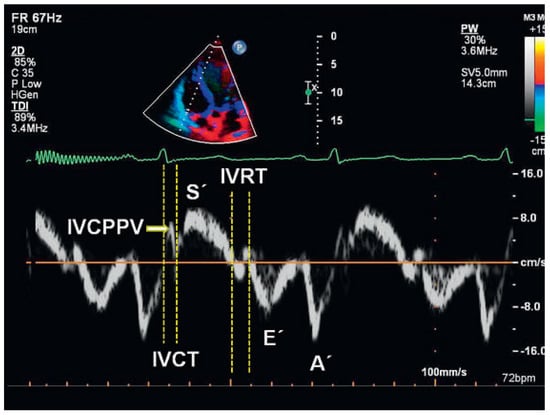

Doppler tissue imaging and regional strain and strain rate

RV diastolic function